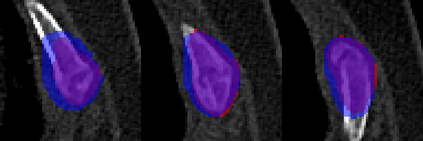

Rib fractures are a common and potentially severe injury that can be challenging and labor-intensive to detect in CT scans. While there have been efforts to address this field, the lack of large-scale annotated datasets and evaluation benchmarks has hindered the development and validation of deep learning algorithms. To address this issue, the RibFrac Challenge was introduced, providing a benchmark dataset of over 5,000 rib fractures from 660 CT scans, with voxel-level instance mask annotations and diagnosis labels for four clinical categories (buckle, nondisplaced, displaced, or segmental). The challenge includes two tracks: a detection (instance segmentation) track evaluated by an FROC-style metric and a classification track evaluated by an F1-style metric. During the MICCAI 2020 challenge period, 243 results were evaluated, and seven teams were invited to participate in the challenge summary. The analysis revealed that several top rib fracture detection solutions achieved performance comparable or even better than human experts. Nevertheless, the current rib fracture classification solutions are hardly clinically applicable, which can be an interesting area in the future. As an active benchmark and research resource, the data and online evaluation of the RibFrac Challenge are available at the challenge website. As an independent contribution, we have also extended our previous internal baseline by incorporating recent advancements in large-scale pretrained networks and point-based rib segmentation techniques. The resulting FracNet+ demonstrates competitive performance in rib fracture detection, which lays a foundation for further research and development in AI-assisted rib fracture detection and diagnosis.